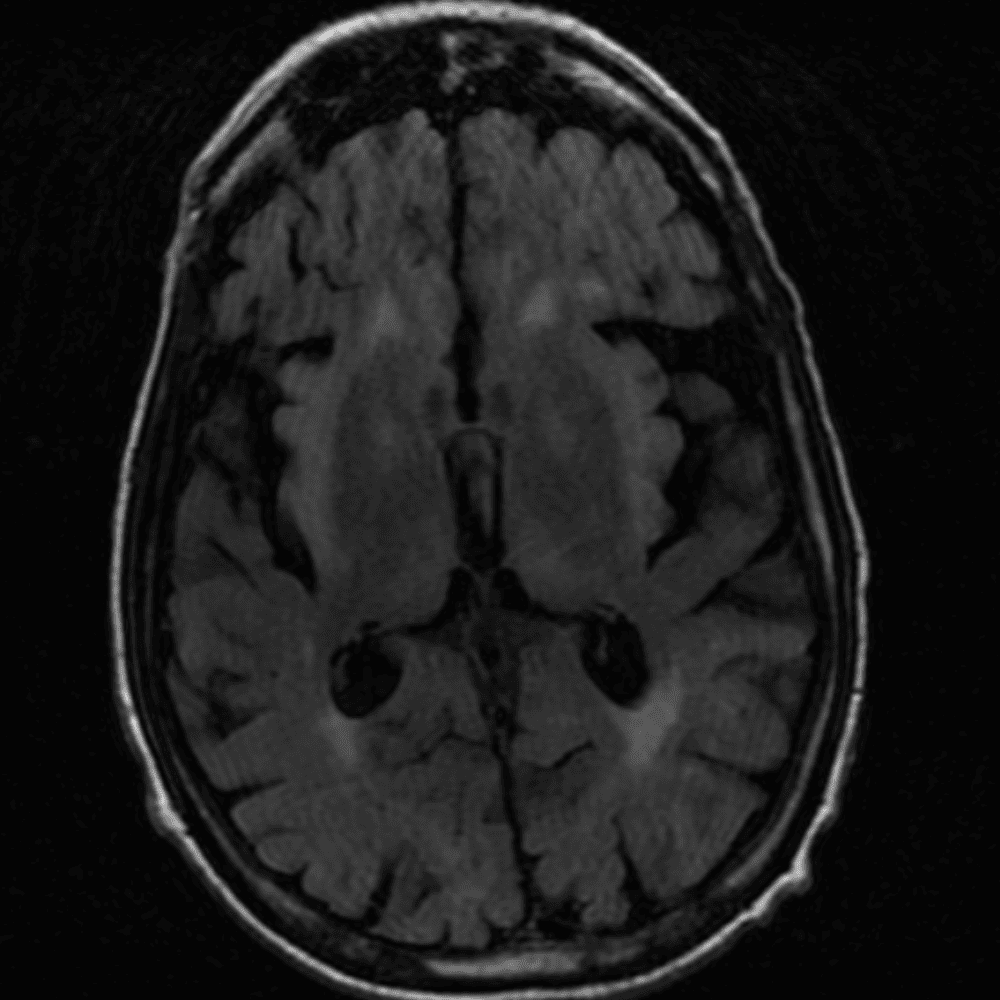

๋‹น์ง ์‹œ ํ”ํžˆ ๋ณผ ์ˆ˜ ์žˆ๋Š” ์‚ฌ๋ก€์˜ ์ „ํ˜•์ ์ธ ์˜ˆ๋ฅผ ํฌํ•จํ•ฉ๋‹ˆ๋‹ค.

39 ์‚ฌ๋ก€

์—ฐ์Šต

๋ฏธ๋ฌ˜ํ•˜๊ฑฐ๋‚˜ ์–ด๋ ค์šด ์‚ฌ๋ก€์™€ ์ผ๋ถ€ ์ •์ƒ ์‚ฌ๋ก€๋ฅผ ํฌํ•จํ•˜์—ฌ ๋‹น์ง์„ ์‹œ๋ฎฌ๋ ˆ์ด์…˜ํ•ฉ๋‹ˆ๋‹ค.

50 ์‚ฌ๋ก€